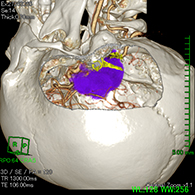

症例1) 65歳男性、頭蓋底部巨大髄膜腫、外科手術のみ

<画像所見>

巨大脳腫瘍を認める。

錐体斜台部巨大髄膜腫を認め、

神経や血管を巻き込んでいる。